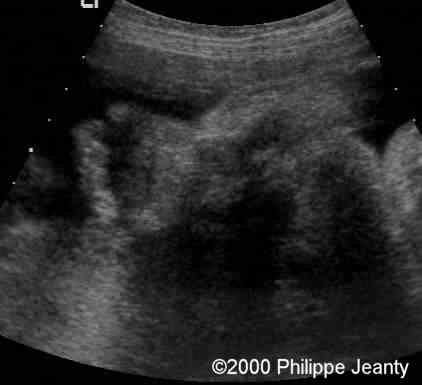

The arm demonstrates too much soft tissue on a too short skeletal frame.

case0020-1

Humerus and femur (below) are too small (see chart below).